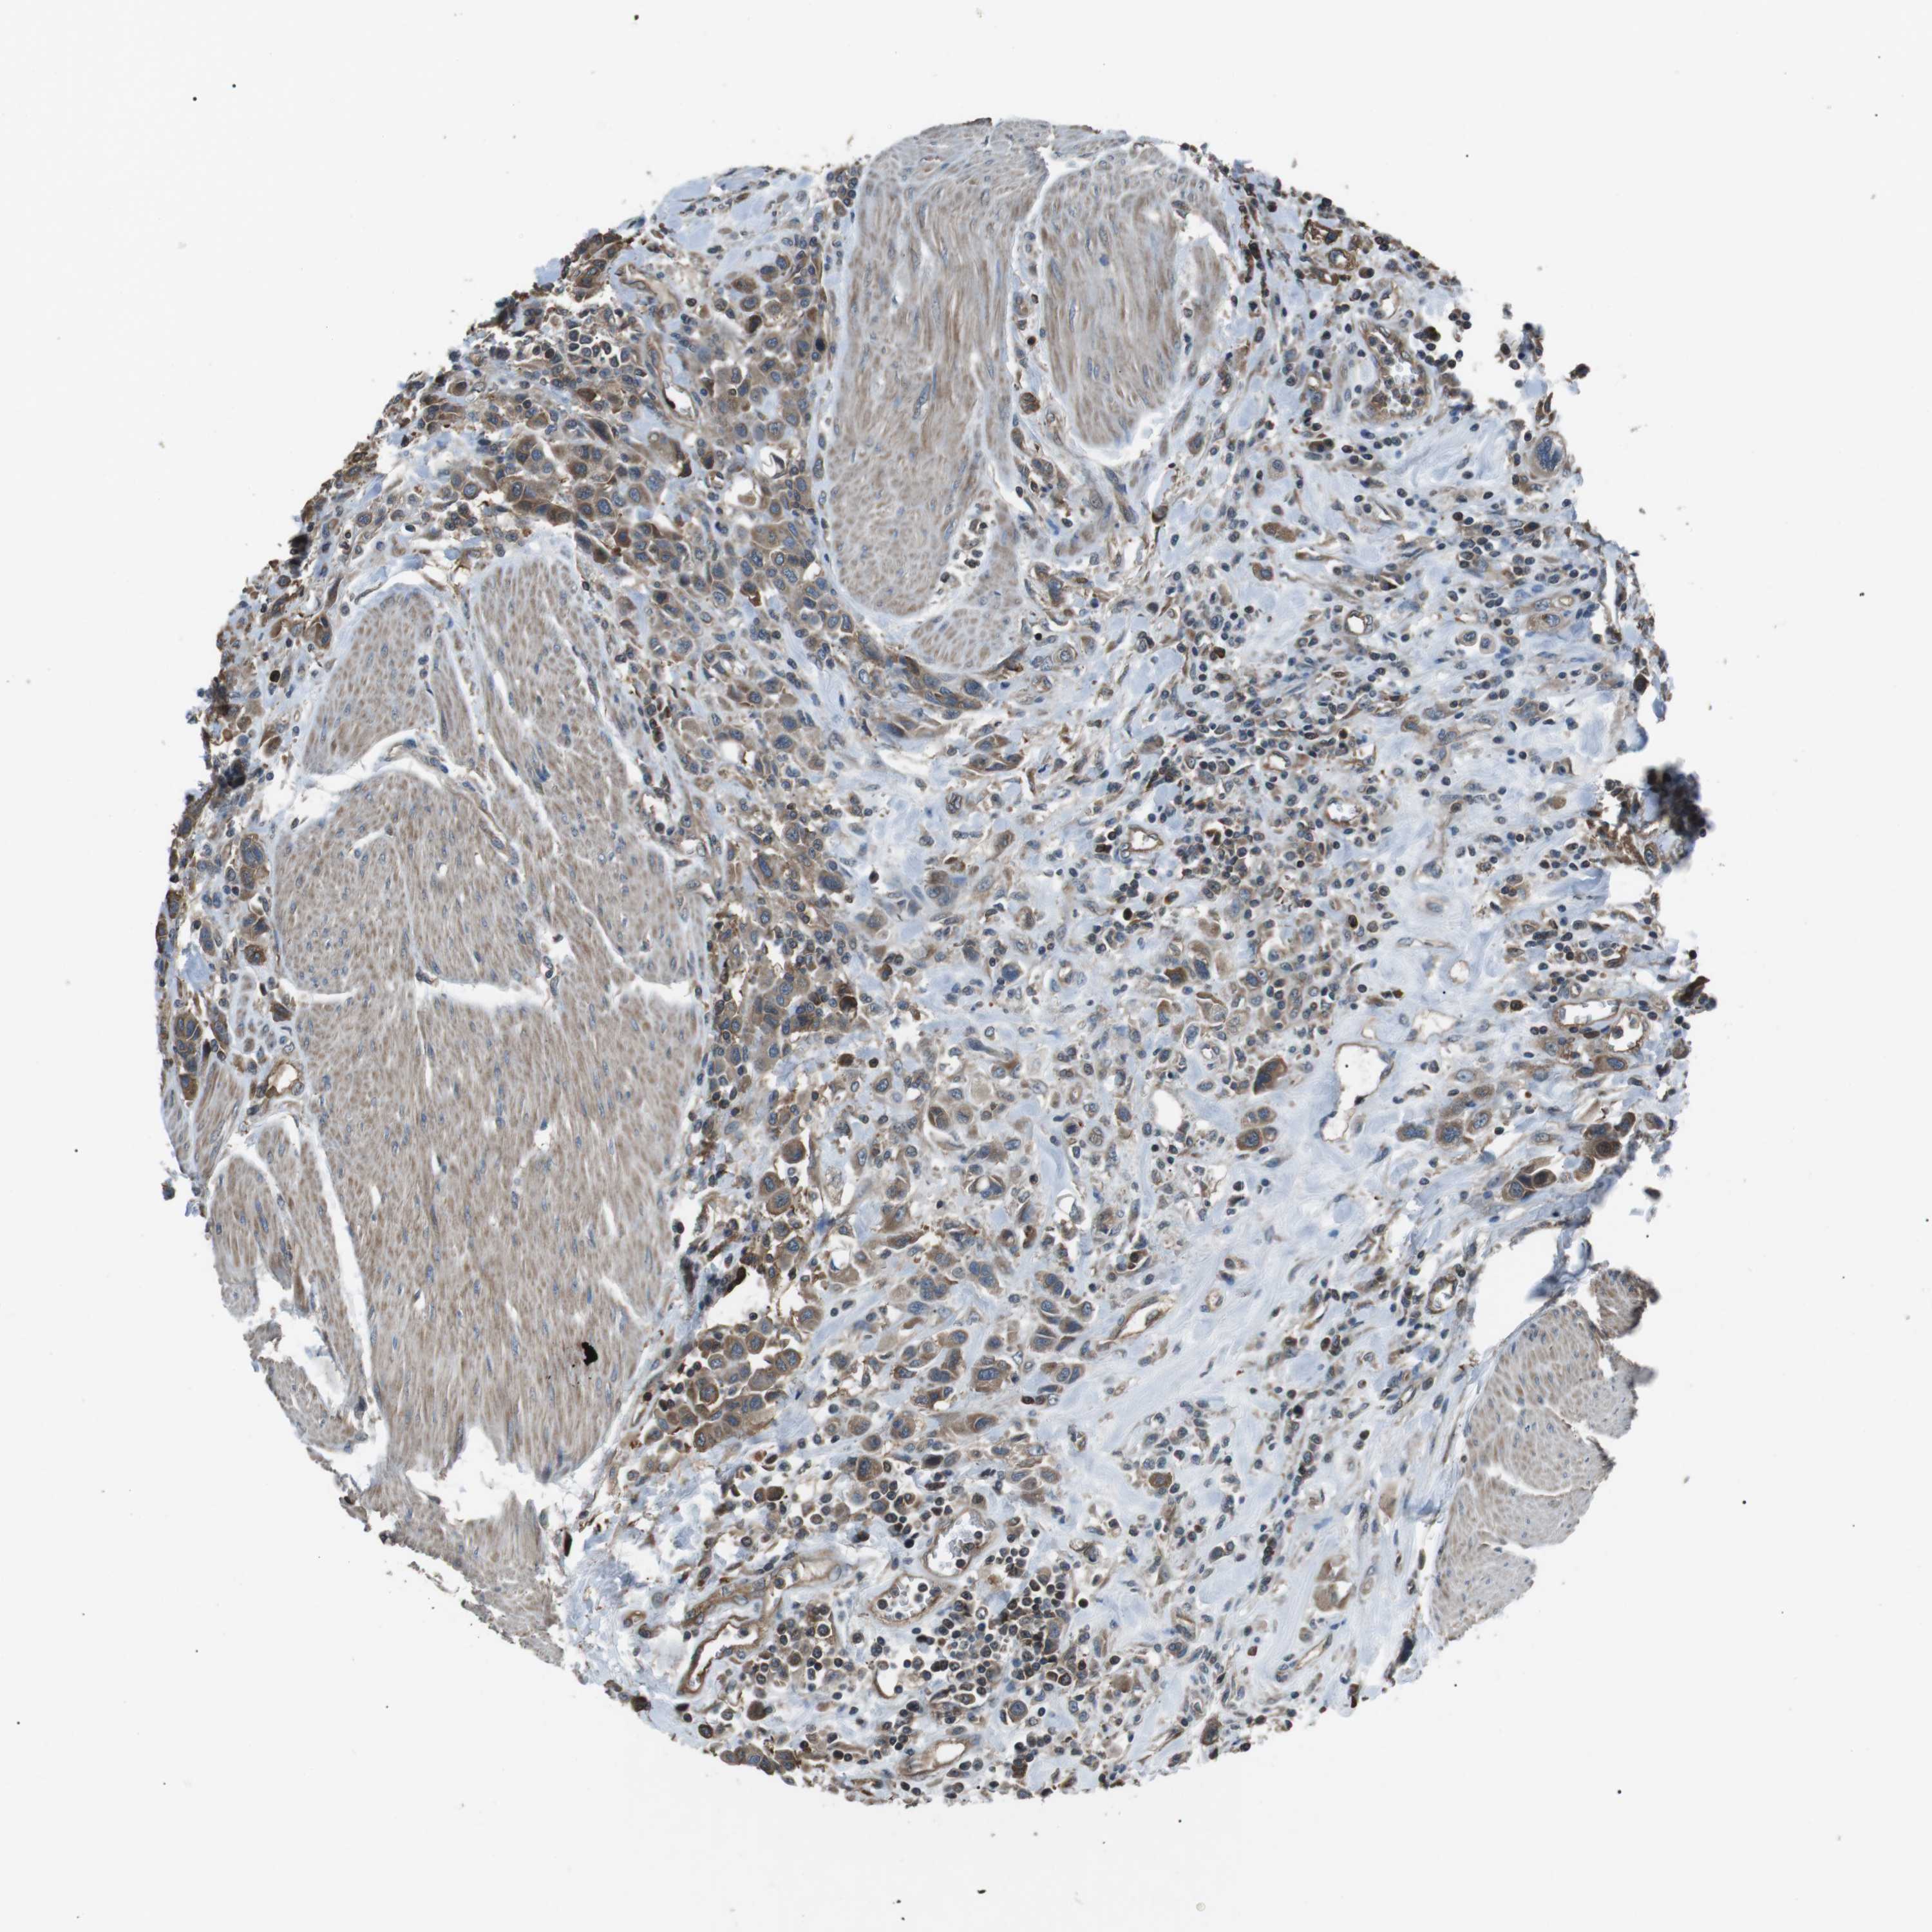

UROTHELIAL CANCER - Protein expressioni

A mouse-over function shows sample information and annotation data. Click on an image to view it in a full screen mode. Samples can be filtered based on level of antibody staining by selecting one or several of the following categories: high, medium, low and not detected. The assay and annotation is described here.

Note that samples used for immunohistochemistry by the Human Protein Atlas do not correspond to samples in the TCGA dataset.

Antibody stainingi

Antibody staining in the annotated cell types in the current human tissue is reported as not detected, low, medium, or high, based on conventional immunohistochemistry profiling in selected tissues. This score is based on the combination of the staining intensity and fraction of stained cells.

Each image is clickable and will lead to virtual microscopy that enables deeper exploration of all samples and also displays staining intensity scores, fraction scores and subcellular localization as well as patient and tissue information for each sample.

Antibody HPA015576

Staining

High

Medium

Low

Not detected

Intensity

Strong

Moderate

Weak

Negative

Quantity

>75%

75%-25%

<25%

None

Location

Nuclear

Cytoplasmic/membranous

Cytoplasmic/membranous,nuclear

Urothelial carcinoma, High grade

Urothelial carcinoma, Low grade